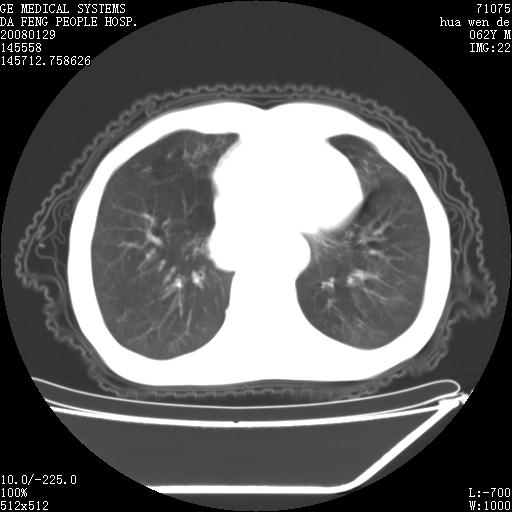

男性,67岁。作肺部检查时发现

理由:1、右上肺内病灶,空洞形成,有液平。

2、肺内多处炎症。

3、前段肺内炎症,支气管引流通畅,与肿块无关系。

1.整个食管扩张,未见明显占位性病变,贲门区亦未见明显占位病变,考虑:贲门失驰缓症;

2.右上肺病变边缘可见毛刺,囊壁厚度不均匀,周围境界较清楚,未见炎性渗出性影,右上肺外带可见片状影,边缘不清,考虑:肺癌伴空洞形成、右上肺炎。

食管全程扩张,壁均匀不厚,喷门失弛缓症

右上肺空洞可见液平,临近肺野磨玻璃密度,考虑1.结核2.脓肿